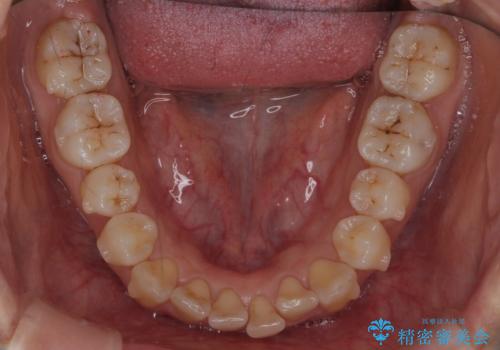

下の前歯のがたつき インビザラインで

- 前歯のがたつきを主訴に来院。

インビザラインで上下の前歯をわずかに削って並べました。

下の歯の叢生を並べると多少ブラックトライアングルがでることがあります。